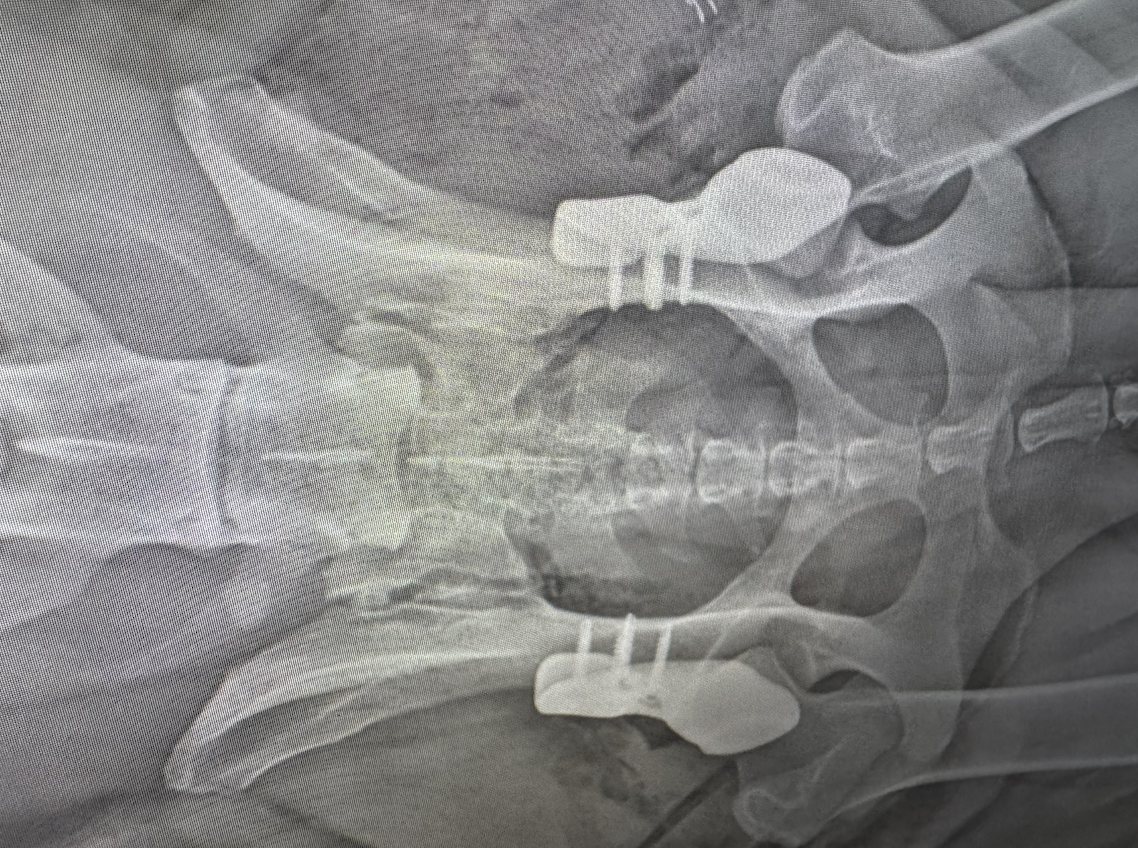

Zum Zeitpunkt der Diagnose war Grammy eine kräftig gebaute, freundliche und verspielte Junghündin. Doch ihr Verhalten änderte sich zusehends: Sie tat sich beim Aufstehen schwer, vermied Treppen und gab selbst beim Ballspiel rasch auf. Schließlich verweigerte sie Spaziergänge ganz und verbrachte den Großteil des Tages liegend. Die orthopädische Untersuchung im Tiergesundheitszentrum List zeigte deutliche Schmerzreaktionen bei der Manipulation der Hüftgelenke sowie eine verminderte Muskulatur an der Hinterhand. Das anschließende HD-Röntgen ergab eine B1-Bewertung – eine leichte Form der Hüftdysplasie, die in Kombination mit den klinischen Symptomen auf eine funktionell relevante Gelenkfehlstellung hinwies.

Um die anatomischen Gegebenheiten exakt zu erfassen, wurde ein hochauflösendes 3D-CT angefertigt. Diese Bildgebung ermöglichte eine detaillierte, dreidimensionale Analyse der Hüftpfanne und des Femurkopfs – ein entscheidender Schritt, um festzustellen, ob Grammy für ein maßgefertigtes 3D-Hüftimplantat infrage kam. Die Auswertung zeigte eine deutliche Deformation der Gelenkpfanne und ein verschobenes Femurkopf-Acetabulum-Verhältnis. Nach interdisziplinärer Beratung wurde Grammy für die Teilnahme an der 3D-HIP-Studie zugelassen – als erste Hündin in Deutschland, bei der dieses Verfahren erprobt wurde.

Der Eingriff wurde im Tiergesundheitszentrum List unter Leitung eines spezialisierten Chirurgenteams durchgeführt. Dank digitaler Operationsplanung konnte die Implantation besonders gewebeschonend und präzise erfolgen. Das individuell gefertigte Titanimplantat wurde in die Hüftpfanne eingebracht und mit bioaktiven Schrauben fixiert. Der Femurkopf blieb erhalten, wodurch die natürliche Kinematik des Gelenks weitgehend bewahrt wurde. Bereits am zweiten Tag nach der Operation begann die Rehabilitation mit passiver Bewegungstherapie. Im weiteren Verlauf kamen Muskelaufbauübungen und gezielte Physiotherapie hinzu. Nach rund sechs Wochen zeigte sich ein eindrucksvolles Ergebnis: Grammy bewegte sich wieder selbstständig, lief ohne sichtbare Schmerzen und begann, ihre Umgebung neugierig zu erkunden – so verspielt wie vor der Erkrankung.